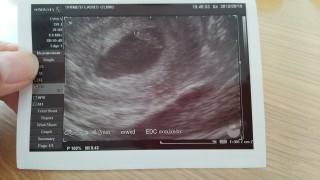

顕微鏡授精にて授かりました。一度の流産を経験していますが、7wでは心拍64程しかなく、CRLも6ミリ程でした。今回は心拍数含め順調とのことです。CRL9.4ミリ。母子手帳持参しましたが、次回の検診から補助券適用のようです。産婦人科は初診で6000円でした。やはり9wを越えないと一般的には不安ですが、今回のこの子は何故か信じられます。穏やかな気持ちでいます。出血も鮮血が1回、茶おりはほぼ毎日ありますが、先生からこの時期の出血は多いので気にしないように言われたので、気にせず前向きに過ごします。